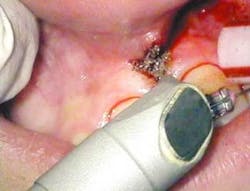

After infiltration of 1cc of local anesthetic solution, the Er:YAG laser (OpusDuo, OpusDent USA) was used at 350mj with a 1,000-micron, contact sapphire tip and heavy water spray to gently ablate the frenal attachment and underlying muscle tissue down to the level of the periosteum (figures 2, 3, and 4). Once this is accomplished, there is a small defect in the vestibular mucosa and interdental papilla where the frenal attachment and muscle once was. There is no charring, no burned tissue, and free bleeding in the site (figure 5).